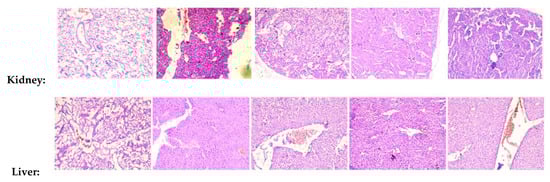

2.12. Arteannuin-B (1) and JR-9 Inhibit Tissue Pathology of Mice

To investigate the effects of 1 and JR-9 on different organ tissues, we assessed the histopathological changes of each group by Hematoxylin-Eosin staining. LPS induces systemic inflammatory responses and injuries on kidney, liver and lung tissues during sepsis.

Several histopathological changes in kidney were observed after LPS treatment. Various parts of the kidney, including renal corpuscles, tubules, blood vessels, and interstitium in the cortex, medulla, and papilla, were examined. Renal epithelial tubular cells were sloughed and decreased epithelial cells in kidney. However, there was no evidence of pathological effects in 1 and JR-9 group.

Similar to kidney injury, LPS-induced liver injury showed significant necrosis. The hepatic morphology and architecture were normal in the control group. Compared to the control group, the LPS group showed obvious inflammatory cell infiltration, cell spotty necrosis, and nuclear pyknosis fragmentation, demonstrating severe septic liver injury which diminished after administration of 1 and JR-9.

In LPS group, Hematoxylin-Eosin stained lungs showed increased thickness of alveolar wall and inflammatory cell infiltration and the control group showed no pathological changes. Pathological changes observed in the BALB/c mice treated with 1 and JR-9 showed weaker changes as compared to the mice treated with LPS. In the microscopic evaluation of the lungs, all the muscular layers and air sacs were examined to reveal no evidence of tissue pathology.

Interestingly, treatment with 1 and JR-9 remarkably treated the injury induced by LPS. The microscopic examination of different tissues showed no significant pathological changes. In the test groups of animals, no toxic or toxic-allergic effects of 1 and JR-9 were found (Figure 9).

Figure 9.

Histopathological analysis of kidney, liver, and lung tissues. BALB/c mice were injected with 1 and JR-9 (40 mg/kg) 1 h before LPS injection (1 mg/kg i.p), and kidney, liver, and lung tissues were harvested 24 h after LPS injection. JR-9 (40 mg/kg) protects the liver, kidney, and lungs from more than 1 (40 mg/kg) damage. These results depict H&E staining of a liver tissue section from the indicated group (40× magnification).